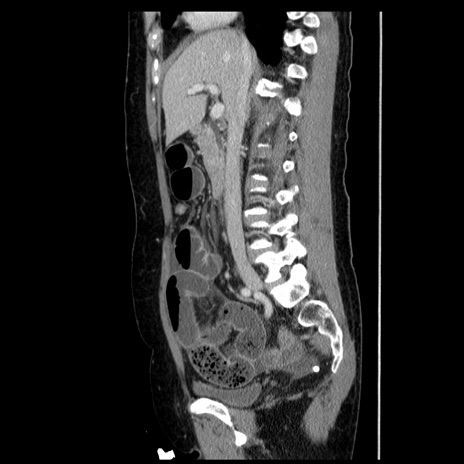

症例6(矢状断像)

【症例】50歳代女性

【主訴】下腹部痛

【現病歴】本日朝より下痢2回あり。 昼食を食べた後、嘔吐3回、下腹部痛認め、症状軽快せず、当院救急搬送。

最終食事:本日昼(生ものなし)。 昨日の夜、刺身を食ぺたとのこと。周囲に同様の症状の者なし。普段、排便は毎日あるとのこと。

【既往歴】卵巣癌術後(8年前に当院で卵巣摘出)

【身体所見】 意識清明、腹部:平坦、腸蠕動音→、やや硬、下腹部自発痛・圧痛あり、反跳痛あり、筋性防御なし。

【データ】WBC 16000、CRP 0.01

横断像